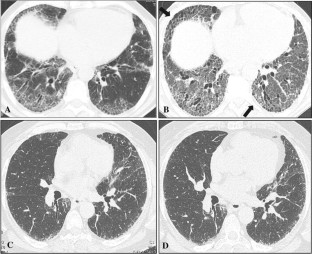

Fig. 1